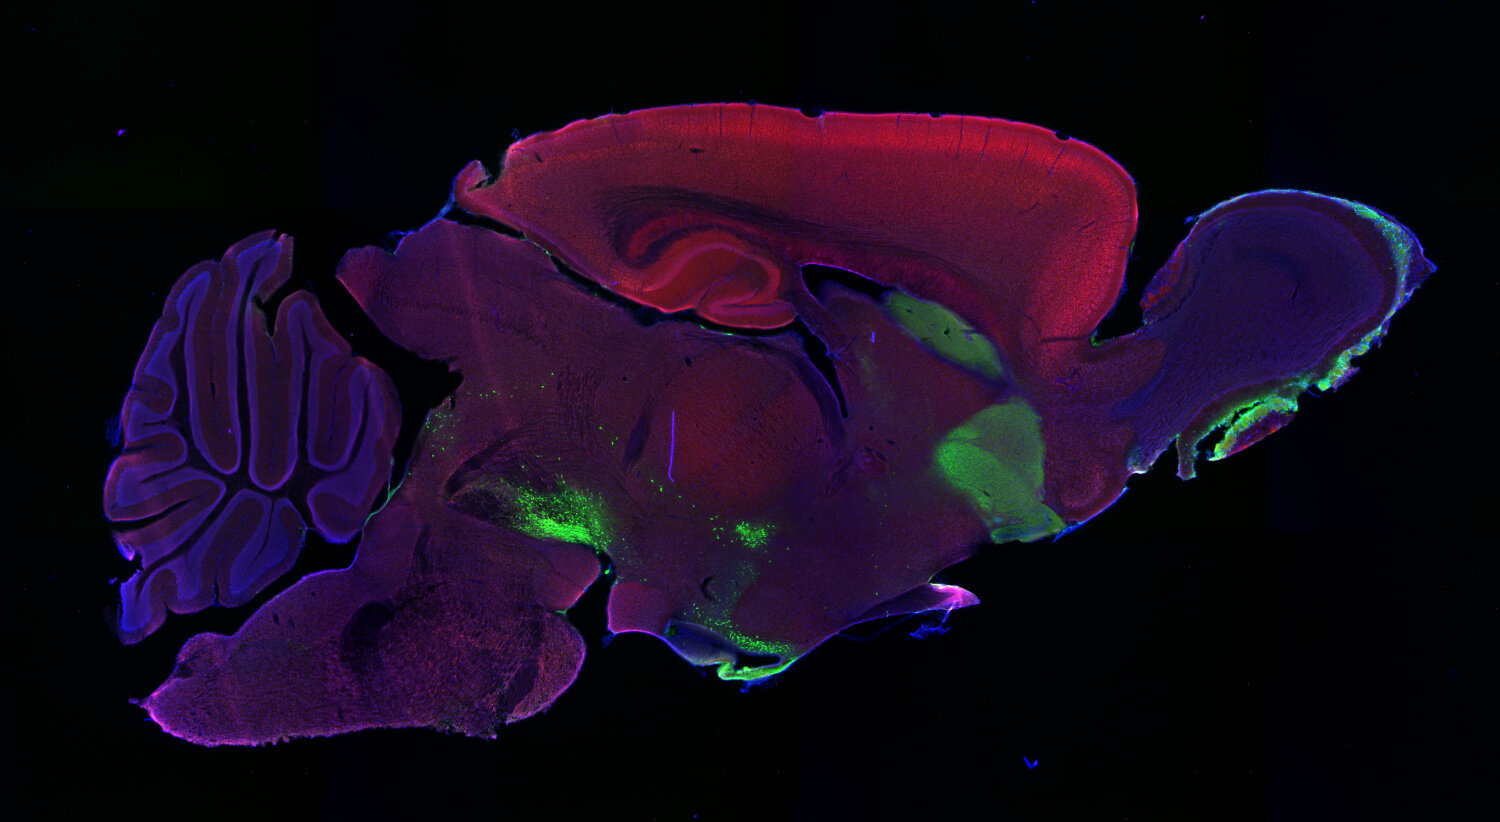

IHC: 1 : 1000 up to 1 : 10000 (see remarks) gallery

Immunohistochemistry (IHC) on 4% PFA perfusion fixed tissue with 24h PFA post fixation. Immunoreactivity is usually revealed by fluorescence or a chromogenic substrate. Some antibodies require special fixation methods or antigen retrieval steps. For details, please refer to the ”Remarks” section.

Cell reports (2023) 423: 112231. 213 211 IHC; tested species: mouse